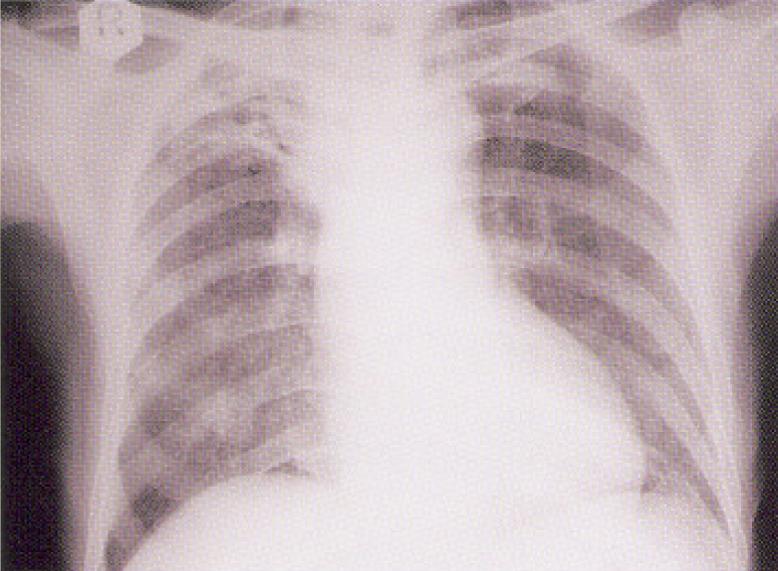

Kan C was a 61-year-old man who is an ex-smoker and lived alone. He had known history of hypertension, gouty arthritis and chronic renal impairment. He presented this time with decrease in appetite for one week associated with cough, sputum and subjective weight loss. Initial CXR was shown as follows: